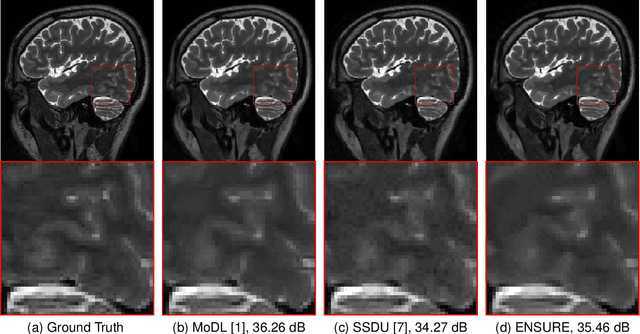

Deep learning accelerates the MR image reconstruction process after offline training of a deep neural network from a large volume of clean and fully sampled data. Unfortunately, fully sampled images may not be available or are difficult to acquire in several application areas such as high-resolution imaging. Previous studies have utilized Stein's Unbiased Risk Estimator (SURE) as a mean square error (MSE) estimate for the image denoising problem. Unrolled reconstruction algorithms, where the denoiser at each iteration is trained using SURE, has also been introduced. Unfortunately, the end-to-end training of a network using SURE remains challenging since the projected SURE loss is a poor approximation to the MSE, especially in the heavily undersampled setting. We propose an ENsemble SURE (ENSURE) approach to train a deep network only from undersampled measurements. In particular, we show that training a network using an ensemble of images, each acquired with a different sampling pattern, can closely approximate the MSE. Our preliminary experimental results show that the proposed ENSURE approach gives comparable reconstruction quality to supervised learning and a recent unsupervised learning method.